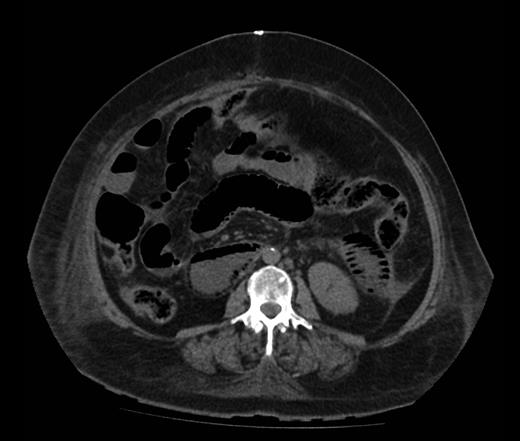

Figure 1 shows a remarkable amount of air in the hepatic portal venous system. Figure 2 demonstrates how the portal vein, splenic vein, superior mesenteric vein and its branches were all outlined with air. Figure 3 shows air within the wall of both small and large bowels. Overall, the radiological findings were suggestive of extensive bowel ischaemia.

Axial image demonstrating intra-mural gas affecting both small and large bowels.